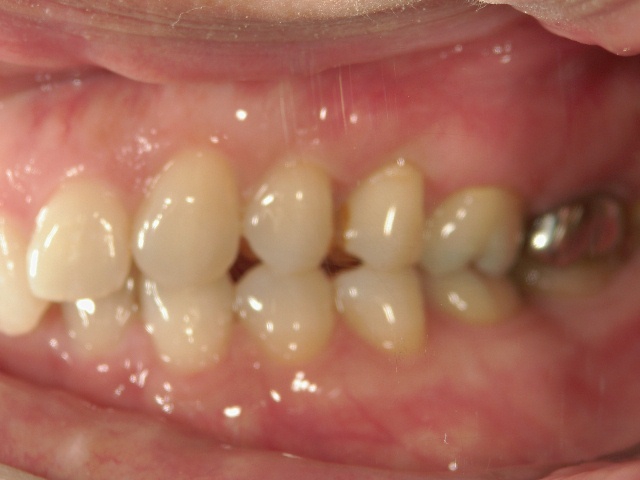

矯正歯科(全顎ワイヤー矯正)治療後

全顎ワイヤー矯正 症例(2)

36歳女性 磐田市

在住

治療期間2年6

ヶ月

矯正歯科 治療後